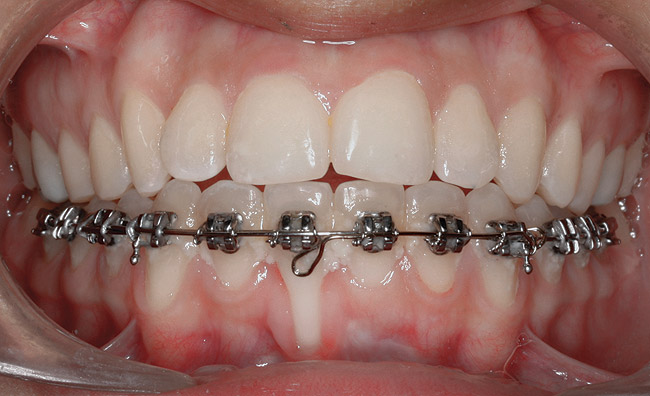

Fig 19. Frontal view showing the orthodontic appliance used in same patient.

Figure 19

A 19-year-old female complaining of gingival recession in the lower right central incisor presented to the authors’ clinic 5 years after completion of orthodontic treatment. The clinical evaluation showed Miller Class II GR accompanied by gingival inflammation (Figure 14). Two years later, despite conservative periodontal treatment, the GR had worsened (Figure 15). The occlusal view shows the presence of a fixed lingual retainer and a significant labial displacement of the root of the affected incisor (Figure 16 and Figure 17). At this stage, orthodontic treatment was considered. The patient was referred for CBCT, which showed no labial bone coverage of the root but 2.5 mm lingual bone thickness at 8 mm distance from the CEJ (Figure 18). After 6 months of orthodontic treatment with fixed appliances (Figure 19), the B-L inclination of the affected tooth was corrected (Figure 20). The frontal clinical view shows narrowing of the GR (Figure 21). Surgical coverage of the exposed root was subsequently performed by connective tissue graft (Figure 22). A long-term stable and esthetic result was achieved (Figure 23).

In cases in which adequate lingual bone thickness (≥2.5 mm) is measured on CBCT, orthodontic retreatment should be encouraged (Figure 6 through Figure 8). Most of these patients present with a fixed orthodontic retainer bonded on the lingual aspect of the lower teeth. Therefore, the crown of the affected tooth is splinted and aligned relative to the adjacent teeth, while only the root is displaced toward the labial alveolar plate. Consequently, the orthodontic movement should consist of lingual root torque around a center of rotation placed in the crown. The torque can be easily achieved with rectangular wires or torqueing springs inserted underneath a heavy round base arch, which provides anchorage from the neighboring teeth.